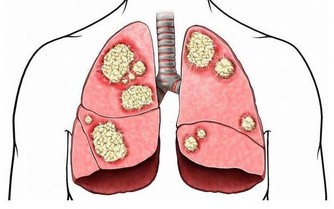

肺部是呼吸系統重要的器官,人們的輕鬆的呼吸、乾淨的血液都依靠肺部的運行。當肺部出現了健康問題,對於整個身體健康是有很大影響的,甚至會危及到生命,所以及時知曉肺部的求救信號是非常重要的。睡覺時有哪些異常情況是肺在求救呢?接下來讓我們一起來了解一下。

1、劇烈的咳嗽

肺部出現健康問題,一個最為重要的症狀就是它會出現劇烈的咳嗽,在夜間甚至會達到影響人睡眠的地步。如果是平常感冒引發的咳嗽,通過及時有效的治療,在幾天之內就能夠好轉,哪怕不去治療也會在兩週之內痊癒。

但是如果咳嗽非常的嚴重,長時間的也無法好轉,尤其是在夜間咳嗽,甚至會影響人的睡眠,這就有可能是肺部出現健康問題的症狀,最有可能是肺炎引起的,如果得不到及時的治療和控制,引發胃癌也是有可能的事。這種情況在吸煙的人身上非常的常見,如果平常愛吸煙,晚上劇烈的咳嗽,一定要去醫院檢查一下肺部,看是否健康。

2、半夜醒來

肺部有疾病的人在半夜經常會醒來,大約會在三到五點之間。之所以會在這個時間醒來,是因為這個時間段是身體的肺部的排毒時間,肺部的功能出現了障礙,人們就會在這個時間段醒來,肺部積累了過多的毒素,疾病也會找上門來。如果經常在這個時間段醒來,千萬不要認為是睡眠出現了問題,單純的去加一些幫助睡眠的措施是沒有辦法解決根本問題的,該醒來的時候還是會醒來。這時候就要仔細的考慮,如果還伴隨著咳嗽等症狀還是應該往肺的方向考慮,檢查一下才能放心。

3、呼吸困難

肺部有疾病的人,首先影響的就是人的呼吸,呼吸對人的重要性恐怕不必再說,呼吸停止了,生命也會走向終結。肺部是呼吸系統重要的器官,肺出現問題,呼吸也會產生異常。當在晚上睡覺的時候,經常的胸悶氣短,甚至呼吸困難,讓人在睡夢中突然醒來,大喘幾口氣才會好轉,就非常有可能是肺部受損嚴重的表現。出現這種情況很有可能是睡眠呼吸暫停綜合症,為了弄清楚原因,還是去醫院檢查一下比較好。

肺部受損是一件比較重大的事,出現了肺部疾病也不要拖延,一定要及早治療,這樣才能把後果盡量的降到最低。